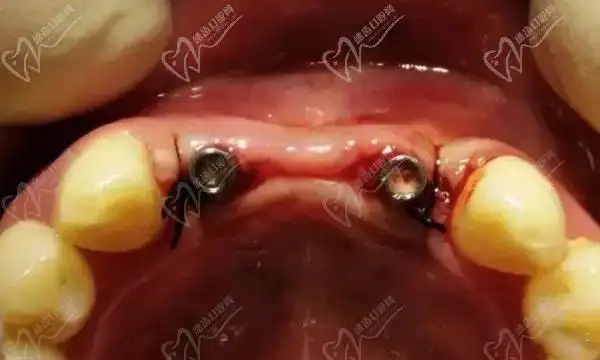

种植牙失败图片